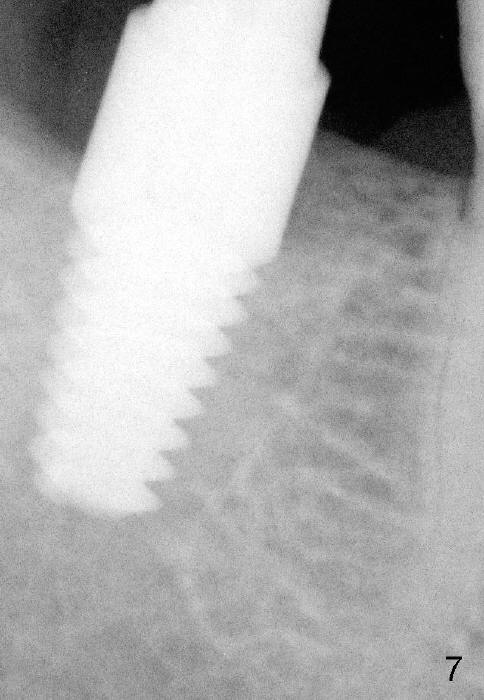

Fig.7: Approximately four months post extraction; immediately post implantation